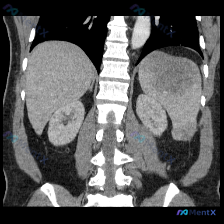

整理了一份最近看到的腹部MRI病例,影像征象非常典型,感觉鉴别思路很有参考价值,分享出来和大家一起梳理下。 --- 影像基础信息 - 序列:腹部MRI T2加权冠状位 - 主要展示:上腹部(肝、脾、双肾、脊柱、腹膜后) 关键影像表现 1. 肝脏:轮廓尚平滑,实质信号基本均匀,未见明确占位。 2. 脾...

各位同道好!最近碰到一份影像读片申请,临床直指「脾脏病变」,但拿到的仅为一张腹部MRI冠状位T2序列图。先整理一下影像科的初步描述和我的分析思路,抛砖引玉和大家讨论。 --- 一、先看影像科给出的「表面事实」 1. 肝脏:形态、实质信号大致均匀,门脉、肝静脉走行清,无明显局灶性高低信号。 2. 脾脏...